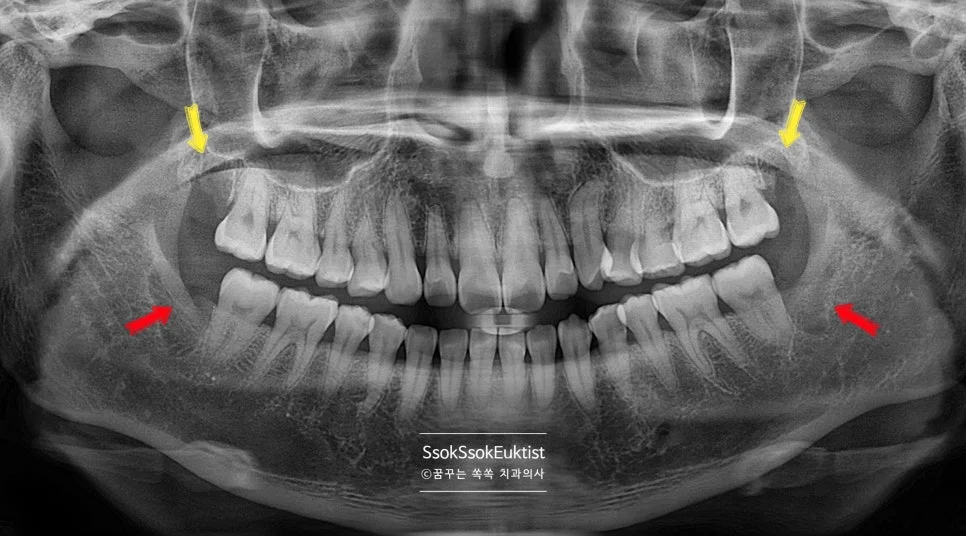

파노라마 진단

사랑니 4개 파노라마 상악 하악 매복 사랑니 제2대구치 표시

파노라마 — 상악 사랑니(노란 화살표)와 하악 매복 사랑니(빨간 화살표) 및 제2대구치 위치 확인

사랑니는 대부분 평생 사용해야 할 소중한 두 번째 큰 어금니(제2대구치) 뒤쪽 부위에 충치나 잇몸 염증을 유발합니다.

더 중요한 점은, 사랑니가 없었다면 이 두 번째 어금니의 뒷면에는 충치나 잇몸 문제가 거의 발생하지 않는다는 사실입니다.

빠르게 발치하는 게 좋은 결정이겠죠?

사랑니 4개 발치 계획 파노라마 상악 하악 화살표 표시

파노라마 — 상악(노란 화살표) + 하악(빨간 화살표) 4개 사랑니 발치 계획